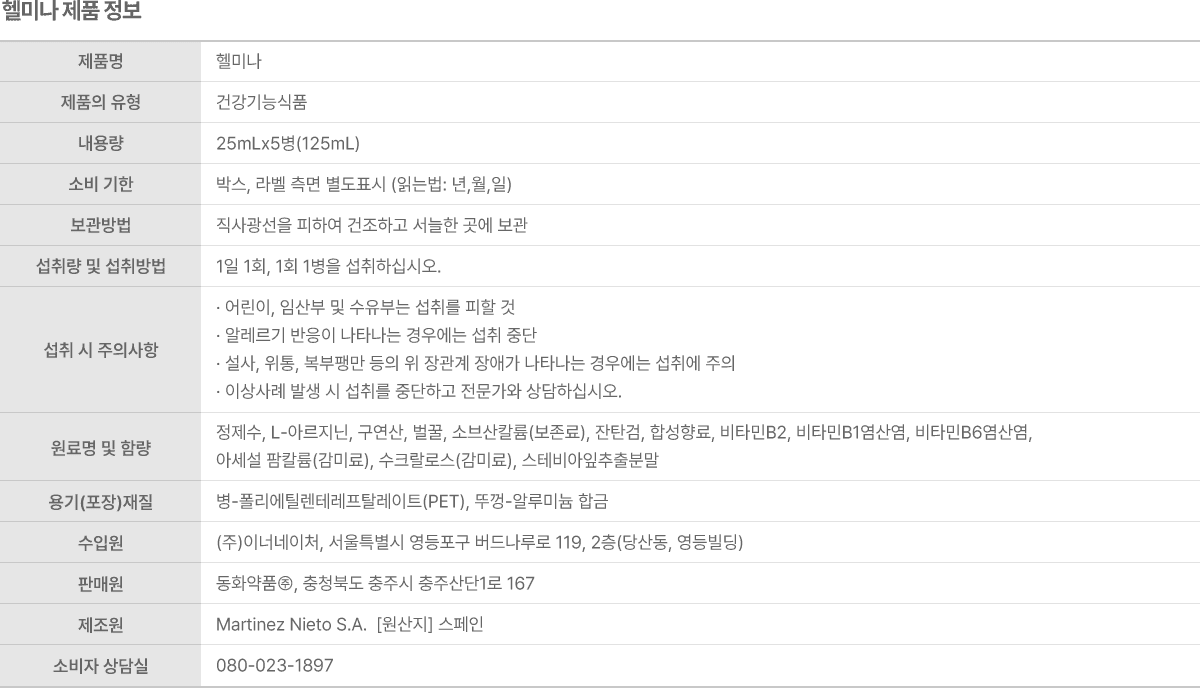

제품 정보 및 유의 사항